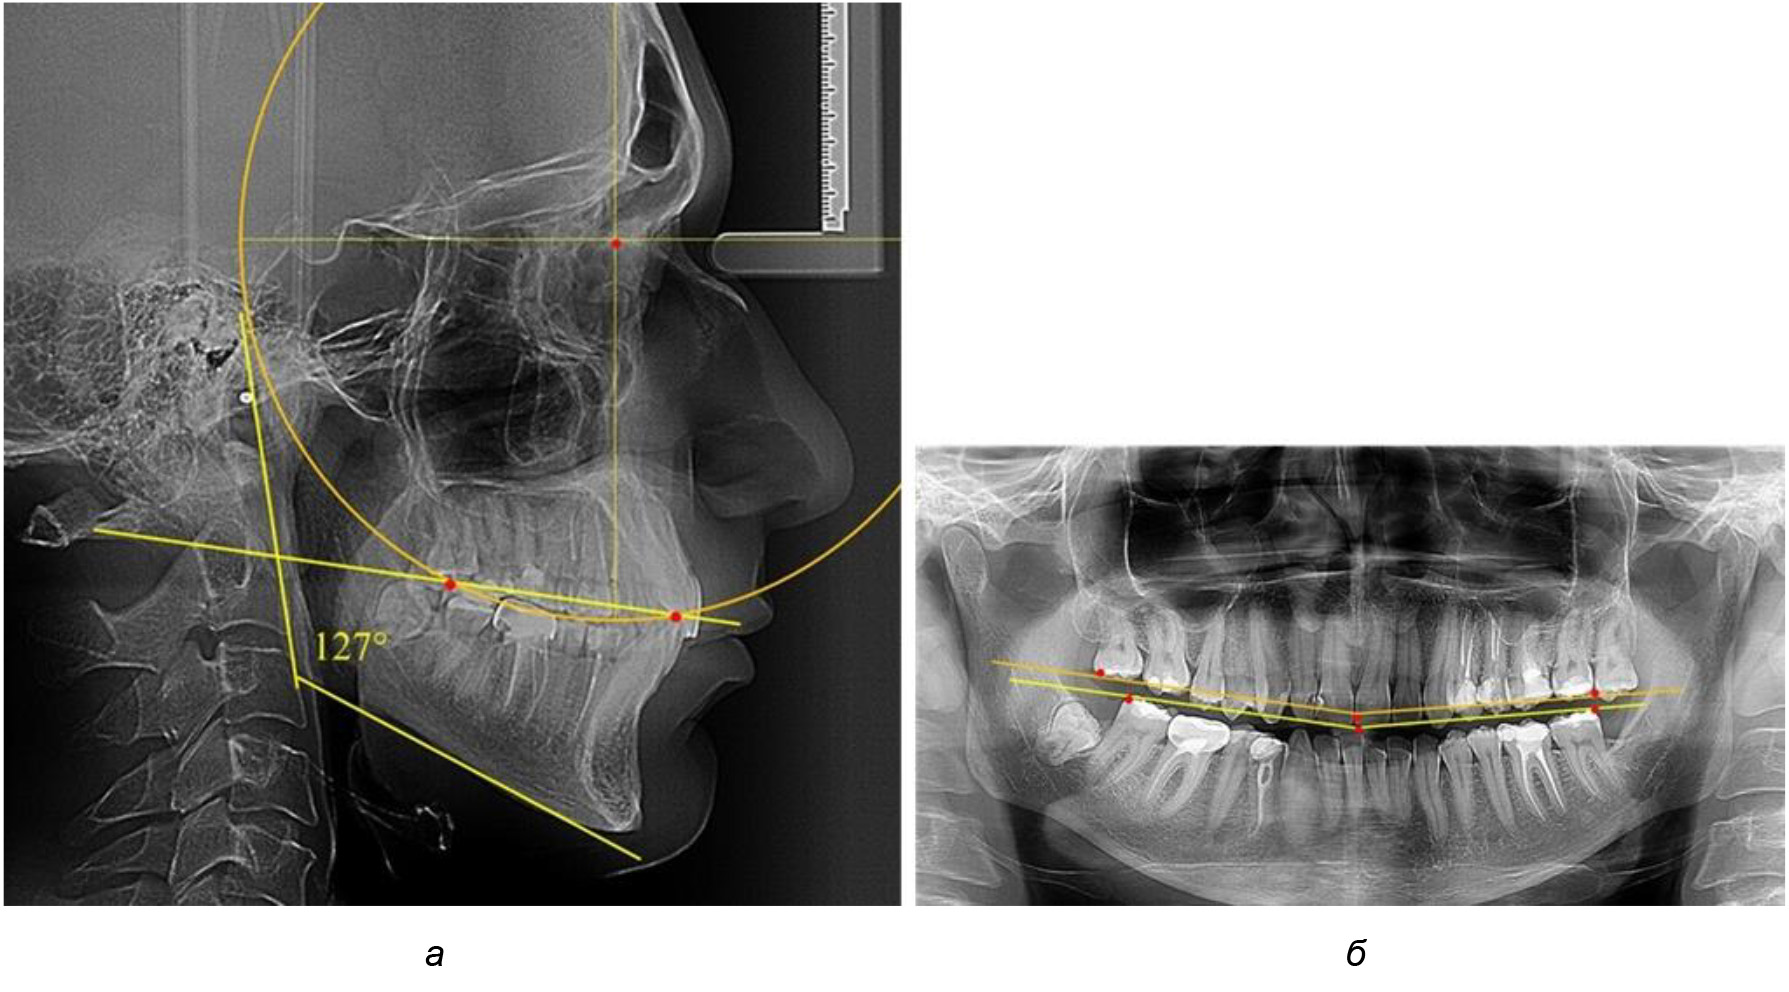

Во 2-й подгруппе 2-й группы было обследовано 7 человек.

Указанная величина не имела достоверного отличия с 1-й подгруппой (р ˃ 0,05), что определяло однородность групп по количественному признаку.

Обращает на себя внимание, что глубина кривой Spee в анализируемой подгруппе практически не отличалась от показателей, полученных у людей с физиологической окклюзией, и составляла (4,23 ± 1,58) мм. Отношение радиуса окружности к сагиттальному размеру окклюзионной линии в среднем по подгруппе составляло 1,623 ± 0,02 и соответствовало числу Фибоначчи.

После лечения пациентов техникой «прямой» дуги, так же как и в 1-й подгруппе, было отмечено увеличение сагиттального размера окклюзионной лини в среднем на (2,38 ± 0,83) мм. Окклюзионная линия практически касалась окклюзионного контура всех жевательных зубов, и отмечалось практически полное отсутствие кривой Spee, так же как и у людей 1-й подгруппы 2-й группы (рис. 6).

Рис. 6. Особенности ТРГ при оптимальной кривой Spee до лечения (а) и после лечения (б) техникой «прямой» дуги

Таким образом, проведенное лечение техникой «прямой» дуги способствует нормализации окклюзионного равновесия и торку передних зубов, однако не соответствует оптимальному окклюзионному статусу, характеризующему физиологическую окклюзию. При этом величина нижнечелюстного угла оставалась на прежнем уровне.